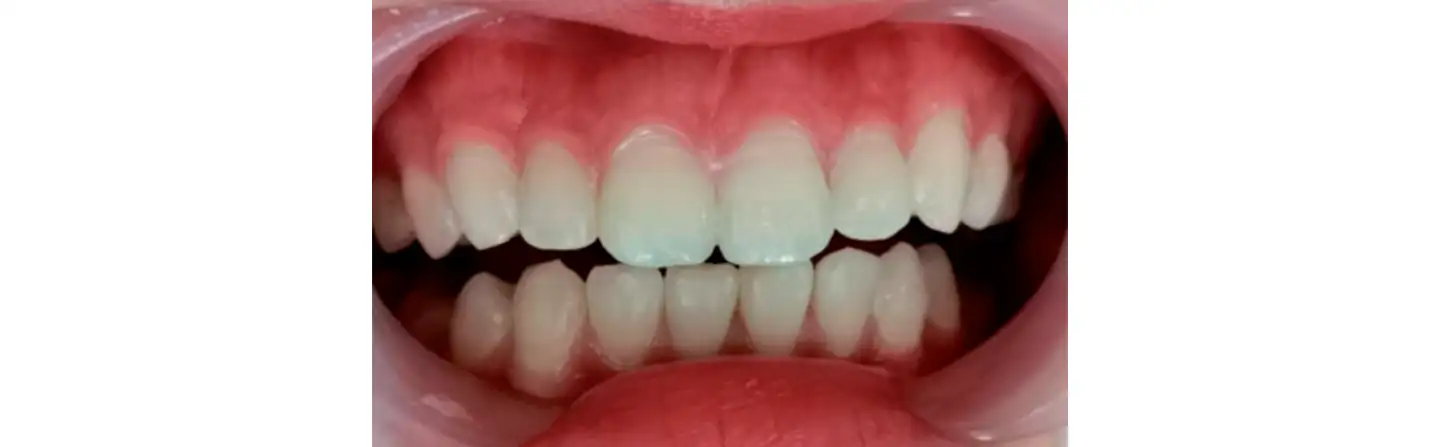

Итоговый показатель флюороза поверхности зуба составил один балл, результат удовлетворил врача и пациента.

Стабильный результат по прошествии двух лет